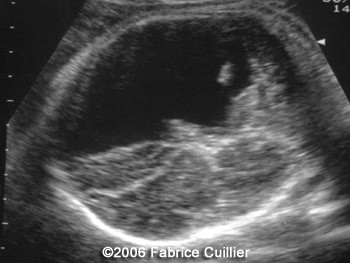

The following images are obtained in a 3rd trimester fetus:

The final diagnosis was: Arachnoid cyst